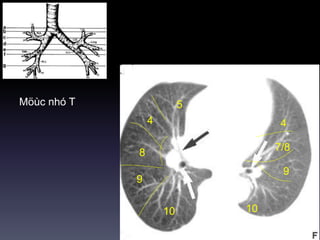

Möùc nhó T

10

5

4

8

9

7/8